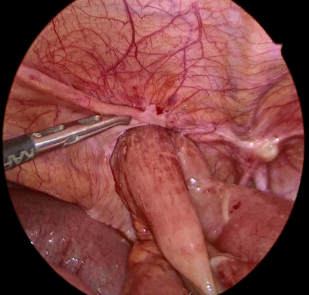

ソケイヘルニア(脱腸)の嵌頓では腸管(主に小腸)や内臓脂肪がヘルニア嚢内に脱出してヘルニア門に挟まれ元に戻らなくなった状態になります。

特に腸管の場合には、腸内の流れが遮断されて腸閉塞になる場合や腸管の血行が遮断されると腸管壊死を起こすことがあります。腸管を切除せざるを得ない場合には治療に時間を要する可能性があります。

腸管を温存できた場合も多くの場合、図のように嵌頓を解除した腸管にダメージを追っており、慎重な術後管理が必要となります。